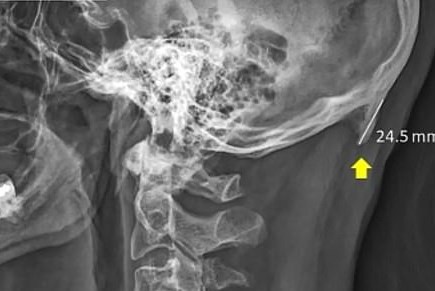

La deformación, también conocida como “protuberancia externa occipital”, puede ser encontrada en la parte baja de la cabeza, justo encima del cuello. Puede ser detectada con los dedos, o en el caso de las personas calvas, incluso es posible verla desde atrás.

Los especialistas analizaron radiografías de personas de 18 a 86 años de edad y encontraron que las protuberancias aparecen en jóvenes de entre 18 a 30 años, quienes consultan sus aparatos móviles al mover hacia adelante la cabeza, la cual puede pesar cerca de 4.5 kilogramos, tanto como una sandía.

El doctor Sahar considera que los “picos” pueden generarse debido a que la mala postura de la espalda añade presión adicional donde los músculos del cuello se unen al cráneo, y el cuerpo responde al crear nuevas capas de hueso. Esto con el fin de ayudar al cráneo a lidiar con el estrés adicional y distribuir su peso en un área más amplia.